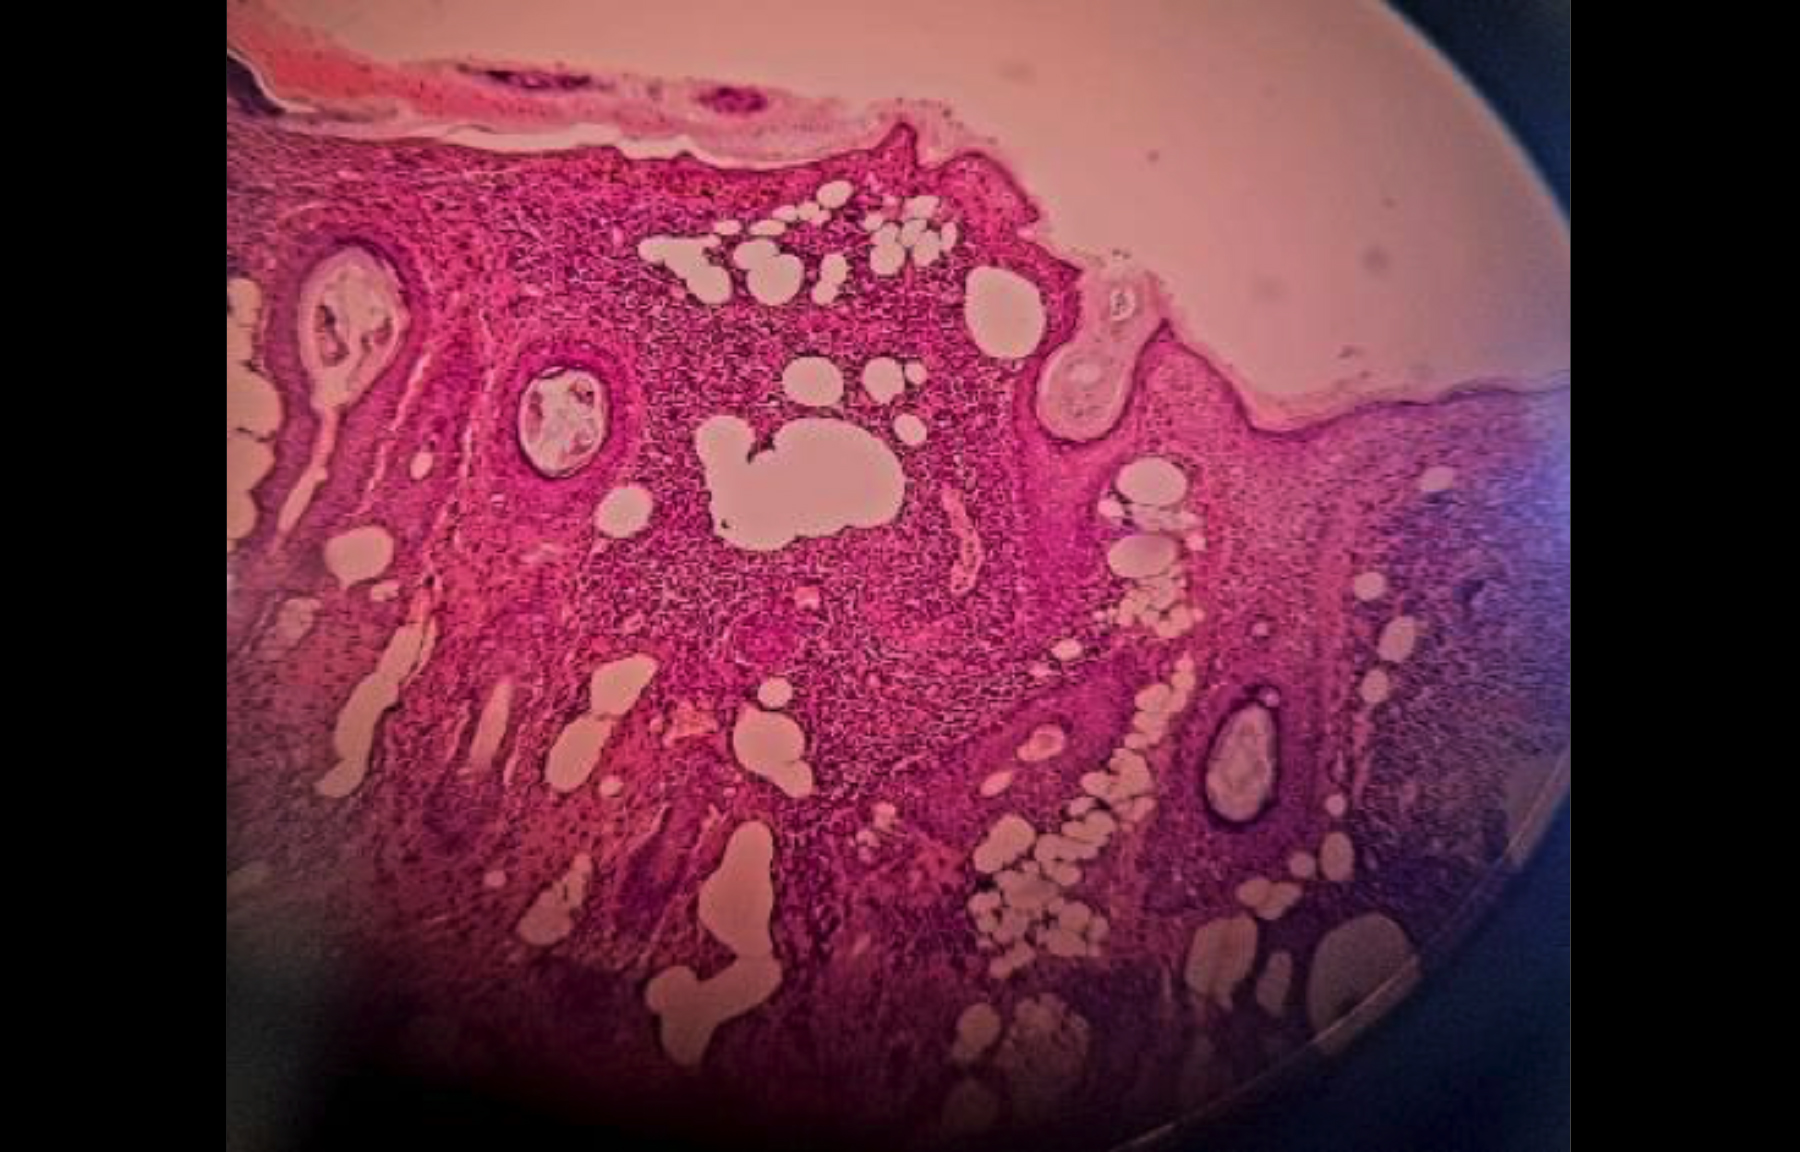

Figure 2: Histopathology image showing heavy lymphocytic infiltrate in the upper dermis.

Flattening of epidermis, basal layer vacuolar alteration, pigment incontinence and a heavy lymphocytic infiltrate in the upper dermis.

A standard 4mm skin punch biopsy was done. Histopathology revealed flattening of the epidermis, basal layer vacuolar alteration, pigment incontinence, and a heavy lymphocytic infiltrate in the upper dermis (Figure 2). Immunohistochemical markers for CD20, CD3, CD4, and CD8 showed a reactive pattern with low Ki-67. Phototesting was not done due to non-availability. Based on clinical presentation, histopathological findings, and literature review, this case was congruent with the classical presentation of a rare newly described entity, LIPEN.

Lichenoid skin disorders are a group of diseases with histopathological features similar to LP. The differentials of lichenoid disorders affecting the face include LP, actinic LP, lichen nitidus, lichenoid medicine eruption, lichenoid graft vs. host disease, and discoid lupus erythematosus.1 But none of these disorders clinically present as pseudovesicles. Histopathology of LIPEN shows focal, heavy lymphocytic infiltrate in the upper dermis with basal layer degeneration and thinning of the epidermis.7 The pseudovesicular appearance of the lesions could be due to epidermal atrophy, but the exact cause remains obscure.2 The special stains, including Ziehl–Neelsen, Alcian blue, and periodic acid–Schiff did not provide additional information.1